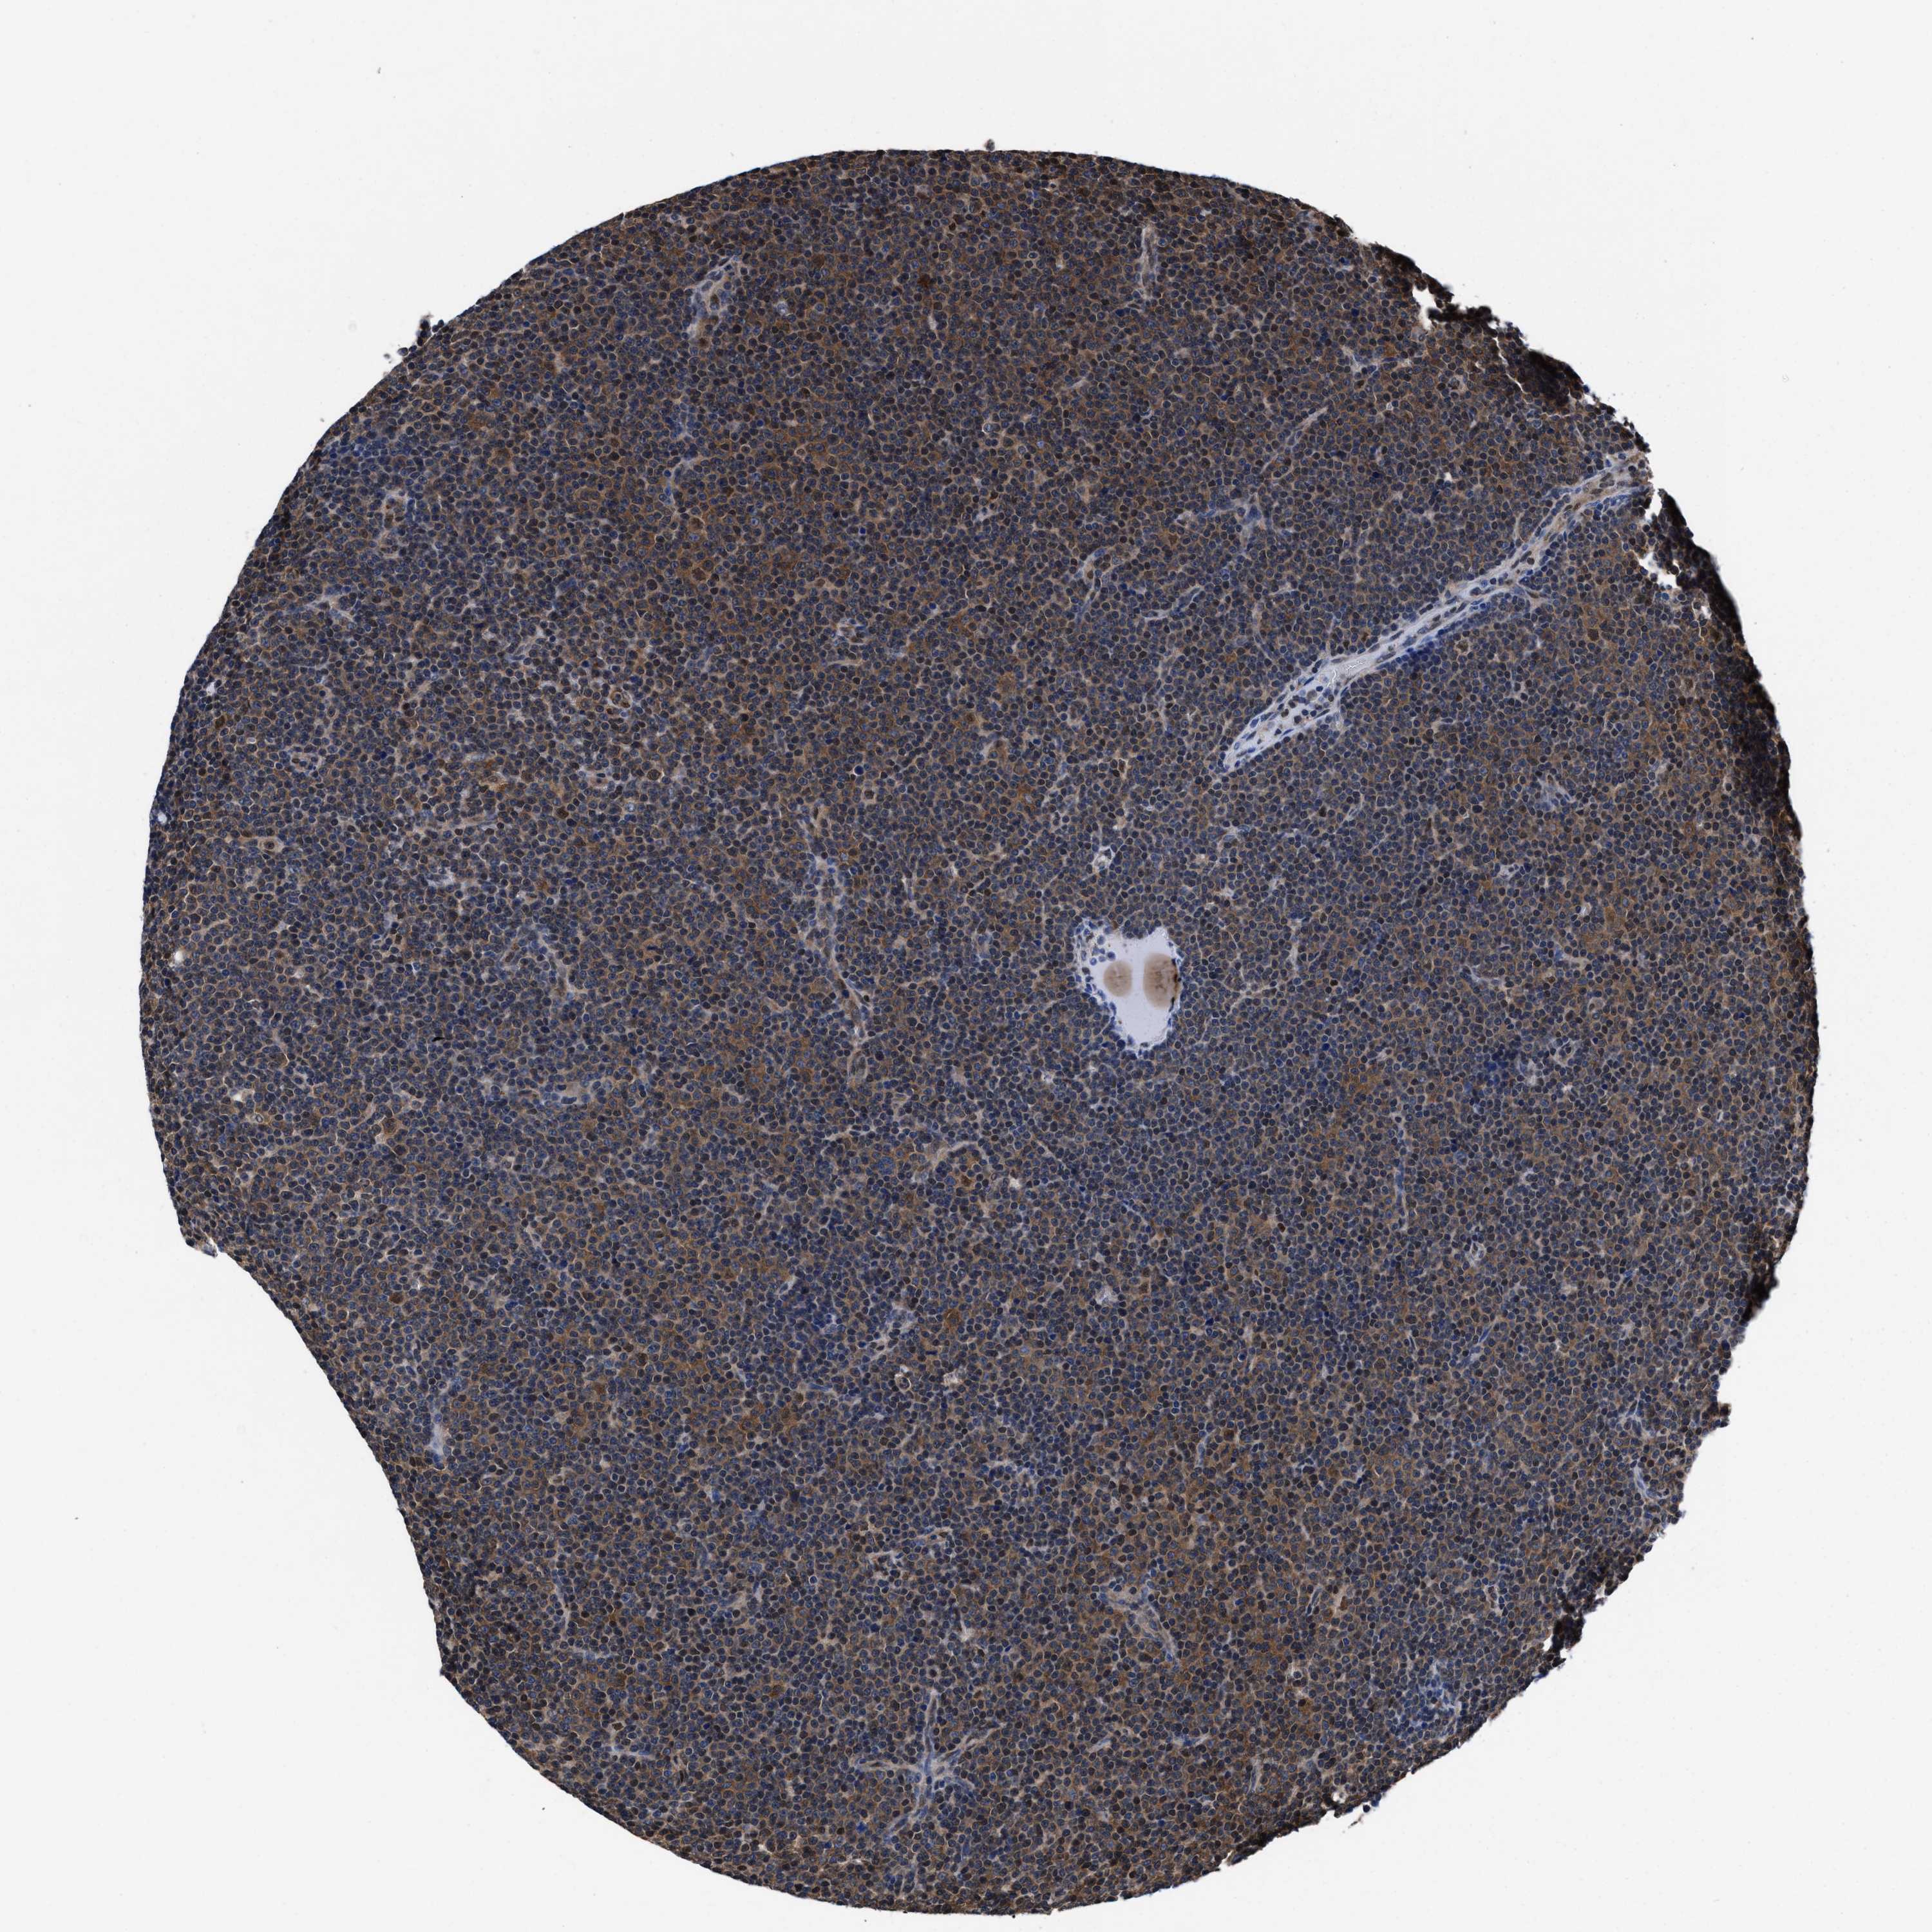

CANCER LYMPHOMA Show tissue menu

LYMPHOMA - Protein expressioni

A mouse-over function shows sample information and annotation data. Click on an image to view it in a full screen mode. Samples can be filtered based on level of antibody staining by selecting one or several of the following categories: high, medium, low and not detected. The assay and annotation is described here.

Antibody stainingi

Antibody staining in the annotated cell types in the current human tissue is reported as not detected, low, medium, or high, based on conventional immunohistochemistry profiling in selected tissues. This score is based on the combination of the staining intensity and fraction of stained cells.

Each image is clickable and will lead to virtual microscopy that enables deeper exploration of all samples and also displays staining intensity scores, fraction scores and subcellular localization as well as patient and tissue information for each sample.